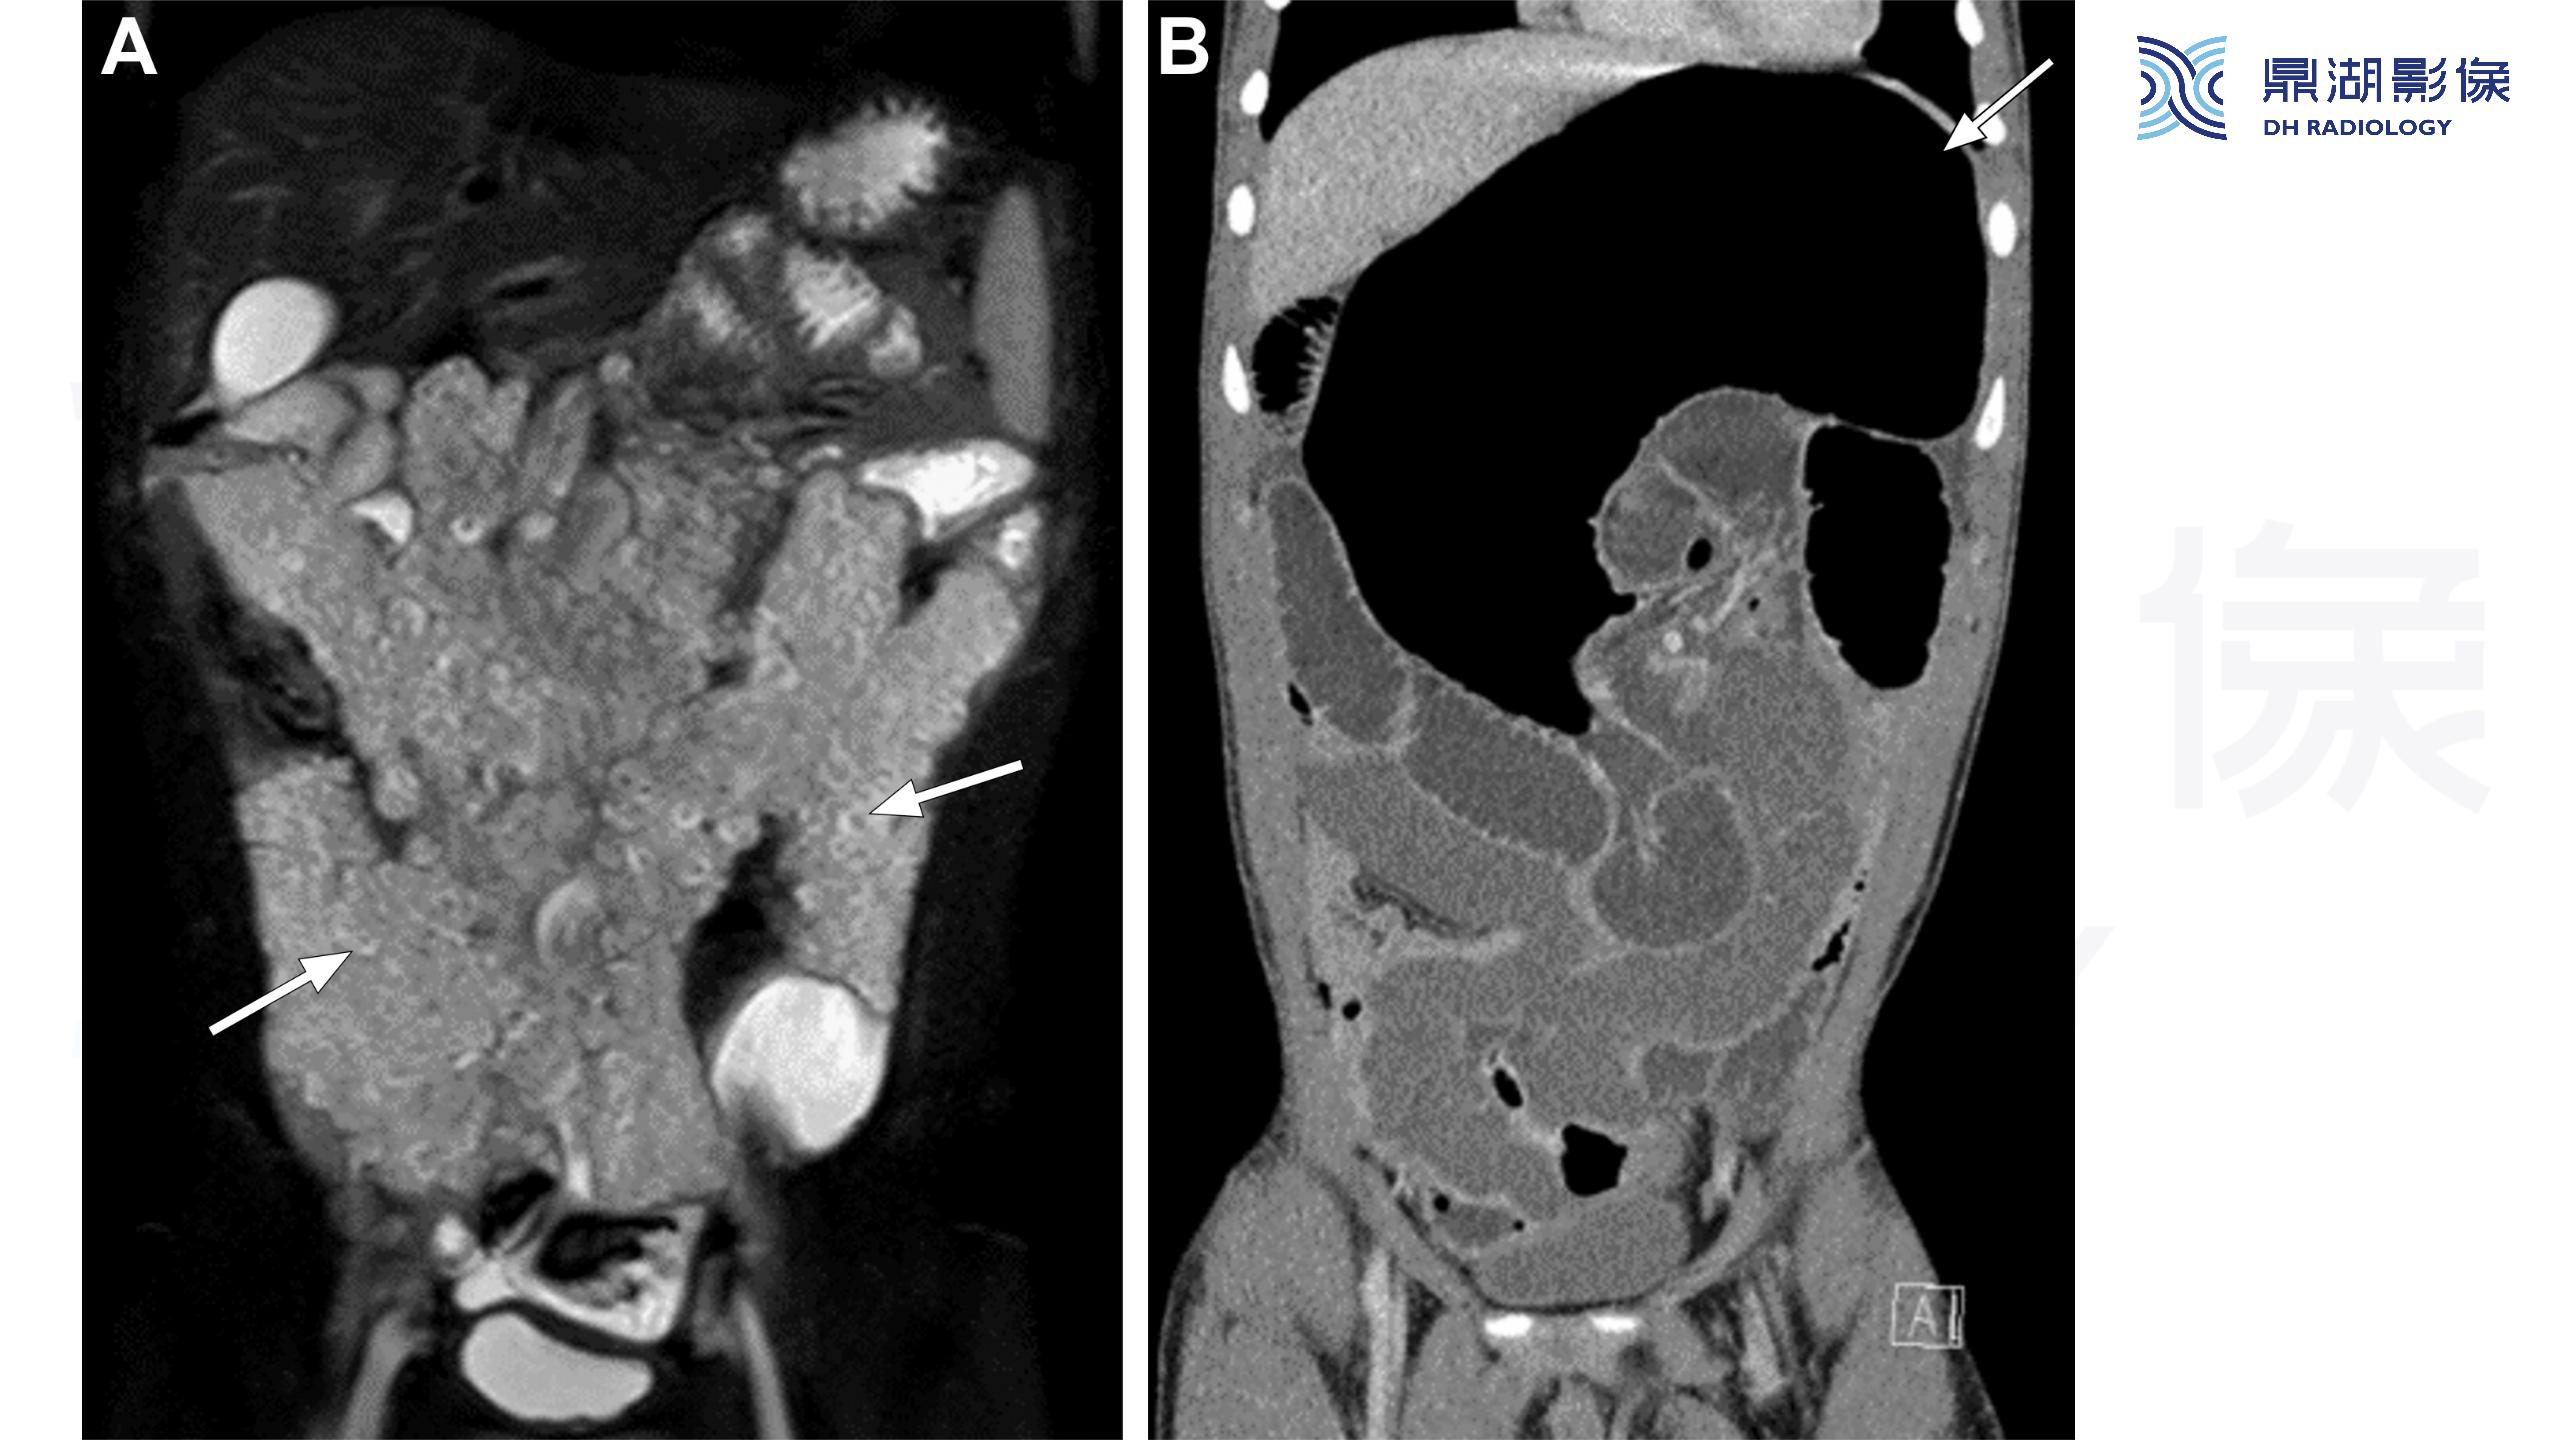

神经纤维瘤病(NF1)